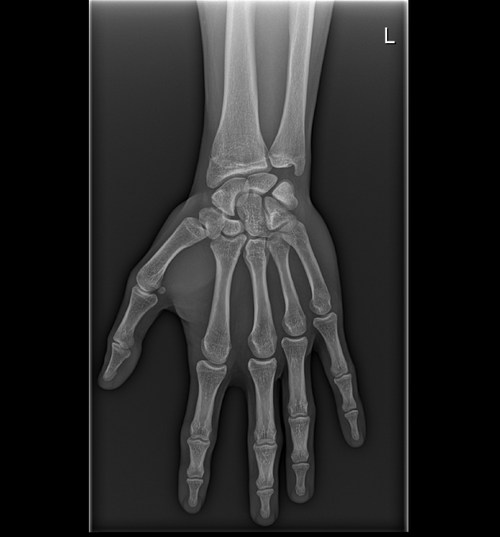

FYI. Im 17yr , 168cm ( 5'6) . my dad is 5'5 and mom is 5'2

the big doc said that my bone age is 17yr old and that my plates are closed but I trust org more then the doctors so here are my results.

is it worth to pin gh or should I accept it?